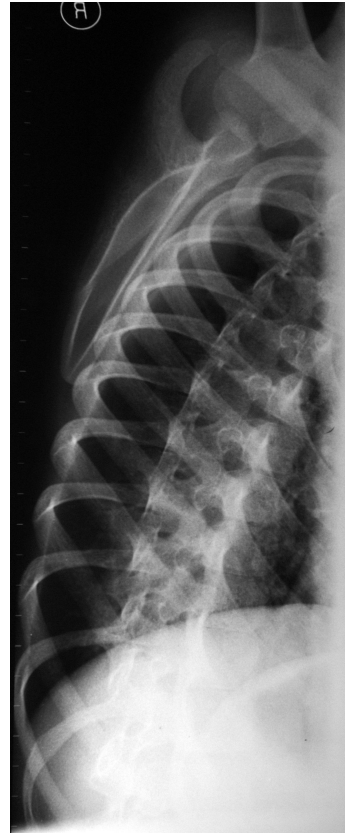

| Figure 3a: good consolidation of the fracture and his realignment |

| Figure 3b: good consolidation of the fracture and his realignment |

Male, 7 years and 9 months old; fell from the dad’s motorbike hitting on the floor the right shoulder. Reached the emergency room immediately after the trauma. At the clinical examination presented swelling and deep pain at the pressure on the coracoid and all over the shoulder; the motility was good but it reawaken/stirred pain in particular in abduction. The standard x-ray carried-out in the emergency room suspecting a fracture of the clavicle or humerus (figureure 1 a-b) underlined a light discontinuity at the base of the right coracoid, centering of the humeral head and continuity of the acromio-clavicular joint. Are requested the specific and comparative projections of the left shoulder (figureure 2 a-b) that highlights the separation of the coracoid base with small compound fracture. Is decided for a conservative treatment by applying Desault bandage for 25 days. At the removal, the clinic examination shows light pain at the mobilization of the shoulder and at the pressure on the coracoid. The radiographic exam points out good consolidation of the fracture and his realignment (figureure 3 a-b). At the clinic follow-up after 20 days after the removal of the bandage, the patient does not complain any pain and presents a complete motility of the shoulder.